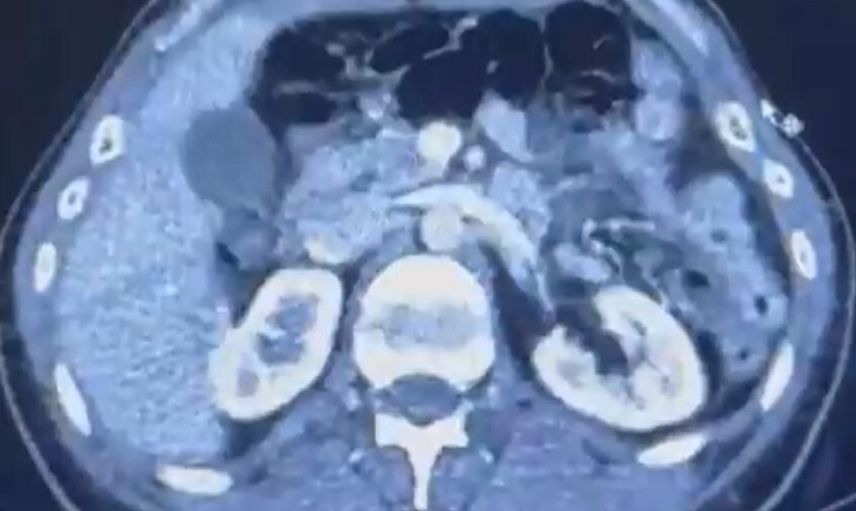

Kayseri Şehir Hastanesi'nde yapılan iç beden muayenelerinde, S.C. ve R.B.C. isimli şahısların mide kısımlarında toplam 50 adet kapsül şeklinde toplamda 554 gram uyuşturucu madde bulundu.

ŞÜPHELİLERİN MİDESİNDE KAPSÜL ŞEKLİNDE YARIM KİLO UYUŞTURUCU MADDE ELE GEÇİRİLDİ.